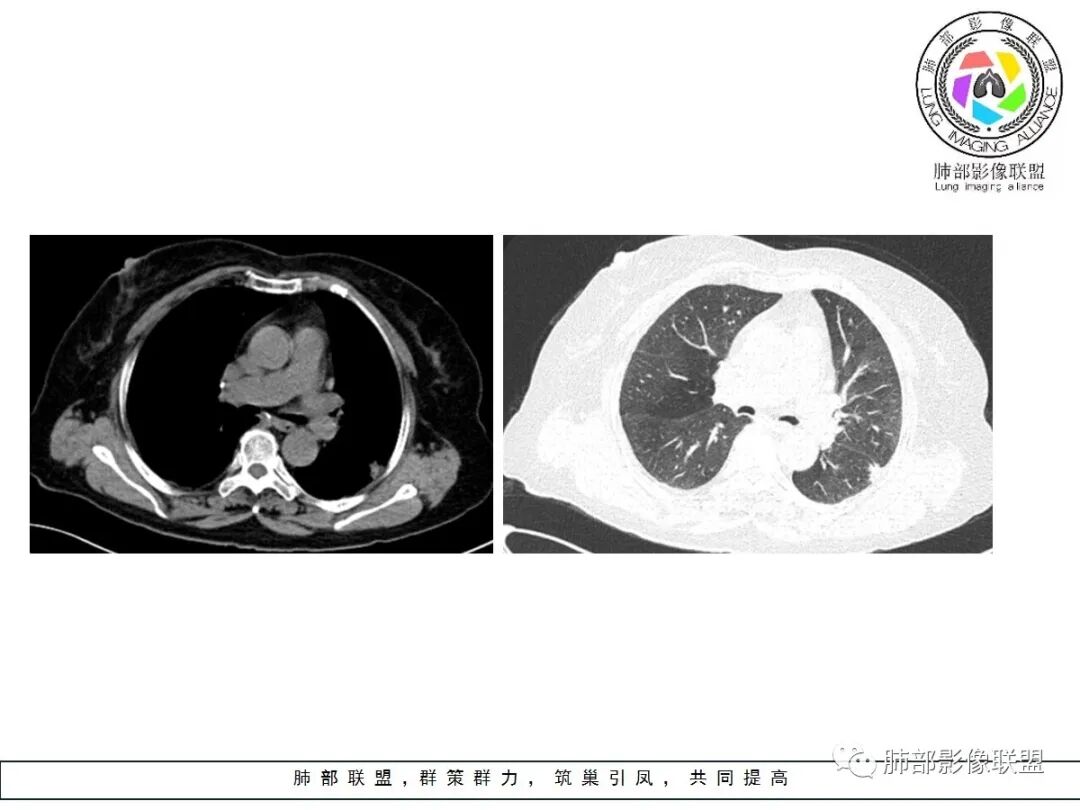

左肺下叶的不规则病灶,有恶性征象,有深分叶,病灶有支气管进入截断了,病灶里支气管扩张;良性征象有平直征,病灶强化明显,脂肪间隙存在,肉芽肿病变鉴别肌纤维母细胞瘤

老年女性,左肺下叶的不规则病灶,深分叶,病灶有支气管进入截断,血管集束,斜裂牵拉,但胸膜干净,有平直征,病灶强化明显,最后还是考虑恶性,鉴别隐球

左肺下叶背段胸膜下不规则结节,有良性征象:有平直、U形凹陷,胸膜下脂肪间隙清晰,明显强化;又有些恶性征象:有分叶,叶间胸膜牵拉。

有些纠结,还是考虑恶性(腺癌可能)> 炎性肉芽肿

临床无特殊。良性征像:冠状位方正,直边征,横断位略呈三角形,尖端指向肺门。恶性征像:小结节堆积样改变,轻度强化,增加20hu左右。横断位多分叶、毛刺。斜裂牵拉内收,胸膜被掀起伴局部少量积液,病灶底部似凸于胸膜外。腺癌与炎性肉芽肿病变的鉴别。强化方式及周边情况,结核可能小。收缩力很大,把腺癌放第一吧。